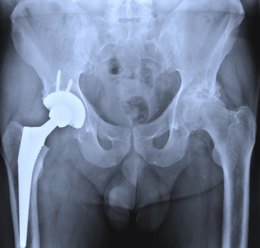

❒ Hip conditions, like arthritis, fracture, gout, or dislocation.

Radiological investigation: It involves Arteriography, Venography or Doppler ultrasound, CT scan of the pubic symphysis, Bone scan, and X-ray of the pelvis and lumbar spine.